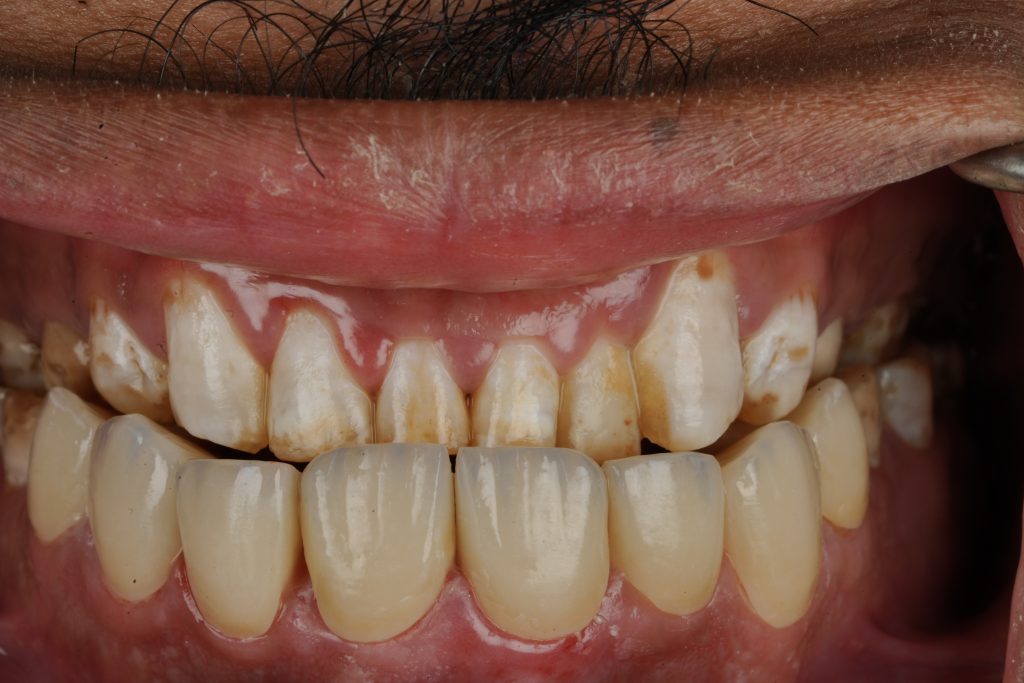

Margins were refined using fine diamond strips, and surface gloss was enhanced with a multi-step polishing system (Shofu OneGloss + OptraPol Next Gen). Post-operative evaluation showed ideal incisal translucency, line-angle symmetry, and gingival health (Fig 5 & 6).

The microscope-guided adhesive workflow delivered lifelike esthetics with optimal functional guidance. The combination of controlled preparation, precision bonding, and lithium-disilicate ceramics resulted in a durable, retrievable, and biomimetic outcome.